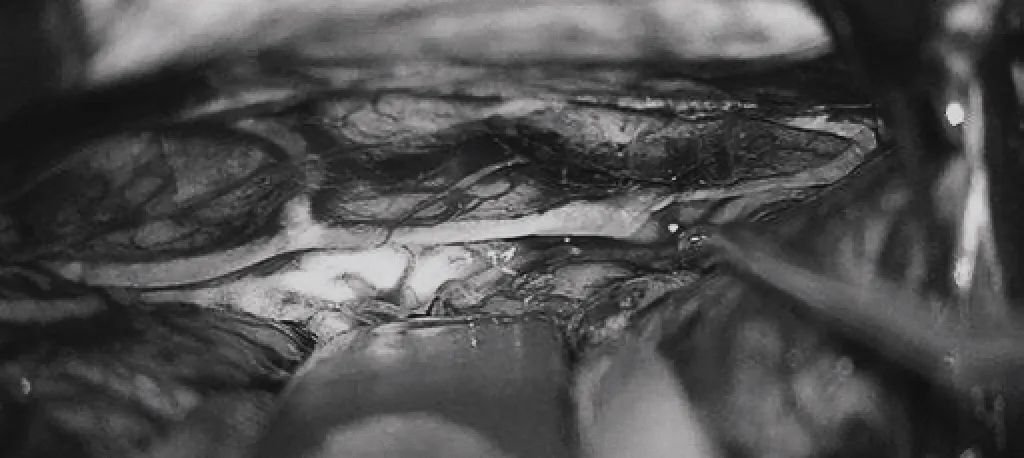

(c)双额开颅,打开纵裂(鼻朝右,中线水平位,重力牵拉右侧半球),显露胼胝体、CmaA和PcaA。(d)切开胼胝体2.5cm,显露透明隔内的AVM,大致显露ACA。

▼(e)将AVM后缘向前牵离穹窿。

▼(f)在透明隔底部保留FoM、穹窿和右侧SepV。

▼(g)引流静脉变黑。

▼(h)引流静脉进入ICV处电凝。完全切除AVM。